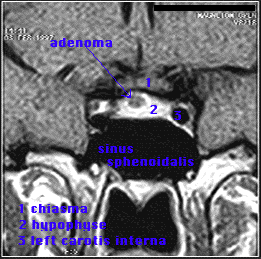

Head and neck cases